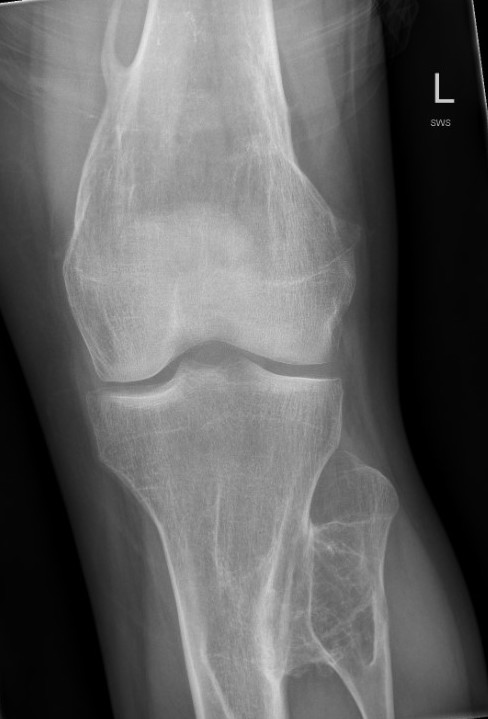

Knee - genu valgum

Genu Valgum OCMultiiple OCMultiple OC

Knee

Knee valgus OCOsteochondroma Knee Lateral

Incidence

Clement et al Knee 2014

- 172 patients with HME

- 90% had exostosis around the knee

- 20% had valgus deformity

- 15% had FFD deformity